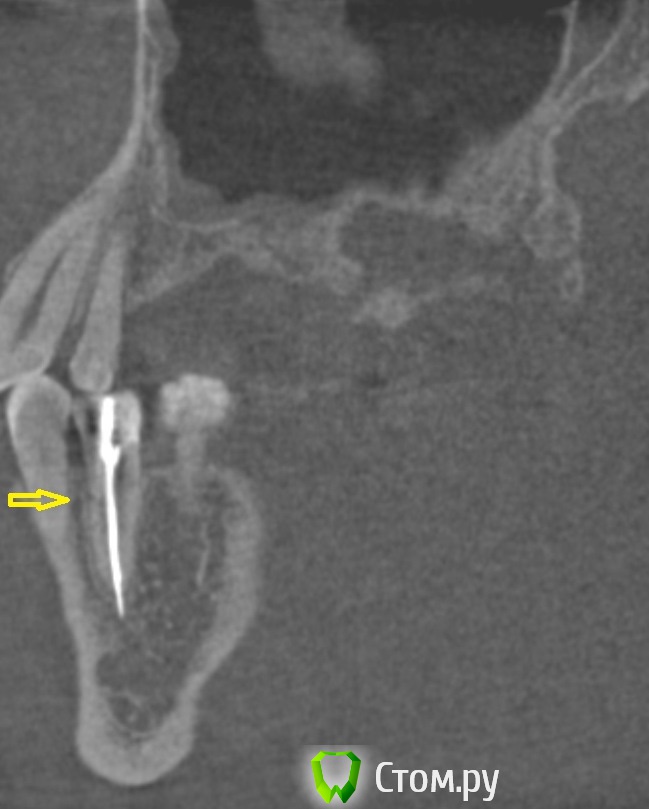

dr-krasnov Опубликовано 10 июня, 2014 Поделиться Опубликовано 10 июня, 2014 (изменено) Тэкс, посмотрел КТ. Претензий к лечению зуба не имею. 4й канал найти не удалось. То был ограниченный артефакт от запломбированного канала. Связи между этим зубом и реакцией слизистой скорее всего нет. Да и синусита нет. Изменения слизистой скорее имеют гиперпластическую природу. Источником исходных реакций послужили уже отсутствующие зубы. Архивные снимки расставили бы все точки над и. Несколько картинок: Небный на осях, можно придраться к незначительному расширению периодонтального пространства апикально, но я бы не стал http://s018.radikal.ru/i515/1406/b8/d712dd4f6158.jpg Дистальный щечный http://s020.radikal.ru/i710/1406/4f/990608ed482a.jpg Мезиальный щечный http://s018.radikal.ru/i518/1406/52/534d8d8534ec.jpg В общем, признаков периодонтита не вижу, рентгенологических показаний для резекции тоже.Я бы порекомендовал динамическое наблюдение. Изменено 10 июня, 2014 пользователем dr-krasnov 1 Ссылка на комментарий

DokDent Опубликовано 10 июня, 2014 Поделиться Опубликовано 10 июня, 2014 Алексей Сергеевич, а это трещина или тоже артефакт? (та же кт) Ссылка на комментарий

dr-krasnov Опубликовано 10 июня, 2014 Поделиться Опубликовано 10 июня, 2014 Если есть сомнения - увеличивайте толщину выделенного слоя. http://s57.radikal.ru/i158/1406/ac/f4ed1bc20195.jpg А вот с 37 беда) http://i031.radikal.ru/1406/e2/2edce574a513.jpg 1 Ссылка на комментарий

DokDent Опубликовано 10 июня, 2014 Поделиться Опубликовано 10 июня, 2014 Если есть сомнения - увеличивайте толщину выделенного слоя. поняла, спасибо А вот с 37 беда) Похоже что виноват медиальный корень? 1 Ссылка на комментарий

dr-krasnov Опубликовано 10 июня, 2014 Поделиться Опубликовано 10 июня, 2014 Трудно сказать однозначно, скорее всего. Ссылка на комментарий